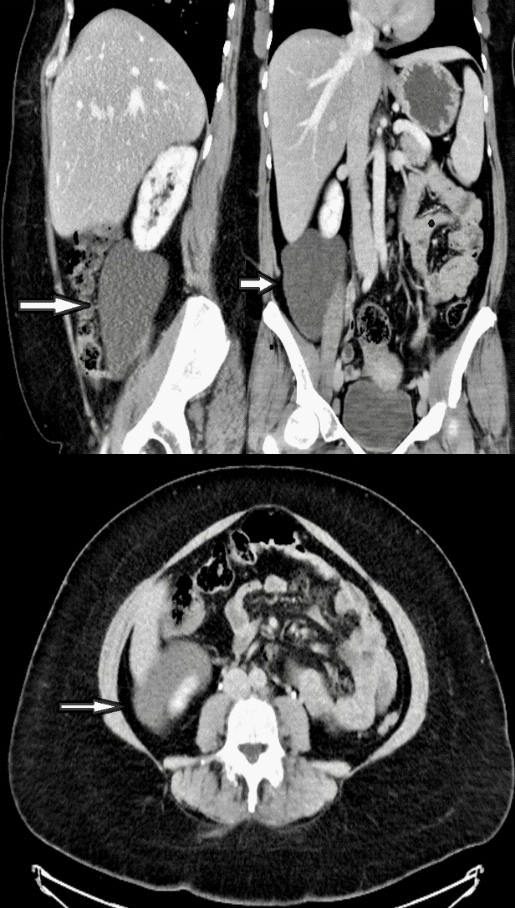

Ultrasound showed small gallbladder polyps and a large cystic lesion in the right abdominal cavity. Contrast enhanced Computed Tomography (CT scan) scan demonstrated a 13 X 9 X 6 cm well-defined fluid filling cystic lesion with fine wall calcifications located in the right retroperitoneal compartment. This lesion is abutting the lower surface of the right kidney, seen extending from inferior border of the right liver lobe to the right psoas muscle. No infiltration to the adjacent organs and no direct attachment to the right ovary noted (Figure 1).

Figure 1:Computed Tomography demonstrating a well-defined fluid filling cystic lesion in the RLQ.